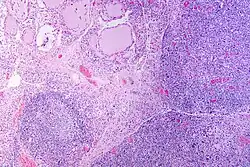

Marked lymphocytic infiltration (purple areas) of the thyroid gland in a patient with chronic autoimmune thyroiditis

High powered magnification showing lymphocytic infiltration of the thyroid gland in autoimmune thyroiditis

Gross pathology of a thyroid with autoimmune thyroiditis may show a symmetrically enlarged thyroid.[5] It is often paler in color, in comparison to normal thyroid tissue, which is reddish-brown.[5]

Microscopic examination (histology) will show lymphocytes (including plasma B-cells) diffusely infiltrating the parenchyma.[55] The lymphocytes are predominately T-lymphocytes with a representation of both CD4+ and CD8+ cells.[5] The plasma cells are polyclonal, with present germinal centers resembling the structure of a lymph node[5] (also called secondary lymphoid follicles, not to be confused with the normally present colloid-filled follicles that constitute the thyroid).[55]

In late stages of the disease, the thyroid may be atrophic.[10] Colloid-filled follicles shrink, and the cuboidal cells that usually line the follicles become Hürthle cells.[5] Fibrous tissue may be found throughout the affected thyroid as well.[5] Severe thyroid atrophy presents often with denser fibrotic bands of collagen that remain within the confines of the thyroid capsule.[55]

Generally, pathological findings of the thyroid are related to the amount of remaining thyroid function — the more infiltration and fibrosis, the less likely a patient will have normal thyroid function.[5] A rare but serious complication is thyroid lymphoma, generally the B-cell type, non-Hodgkin lymphoma.[24]